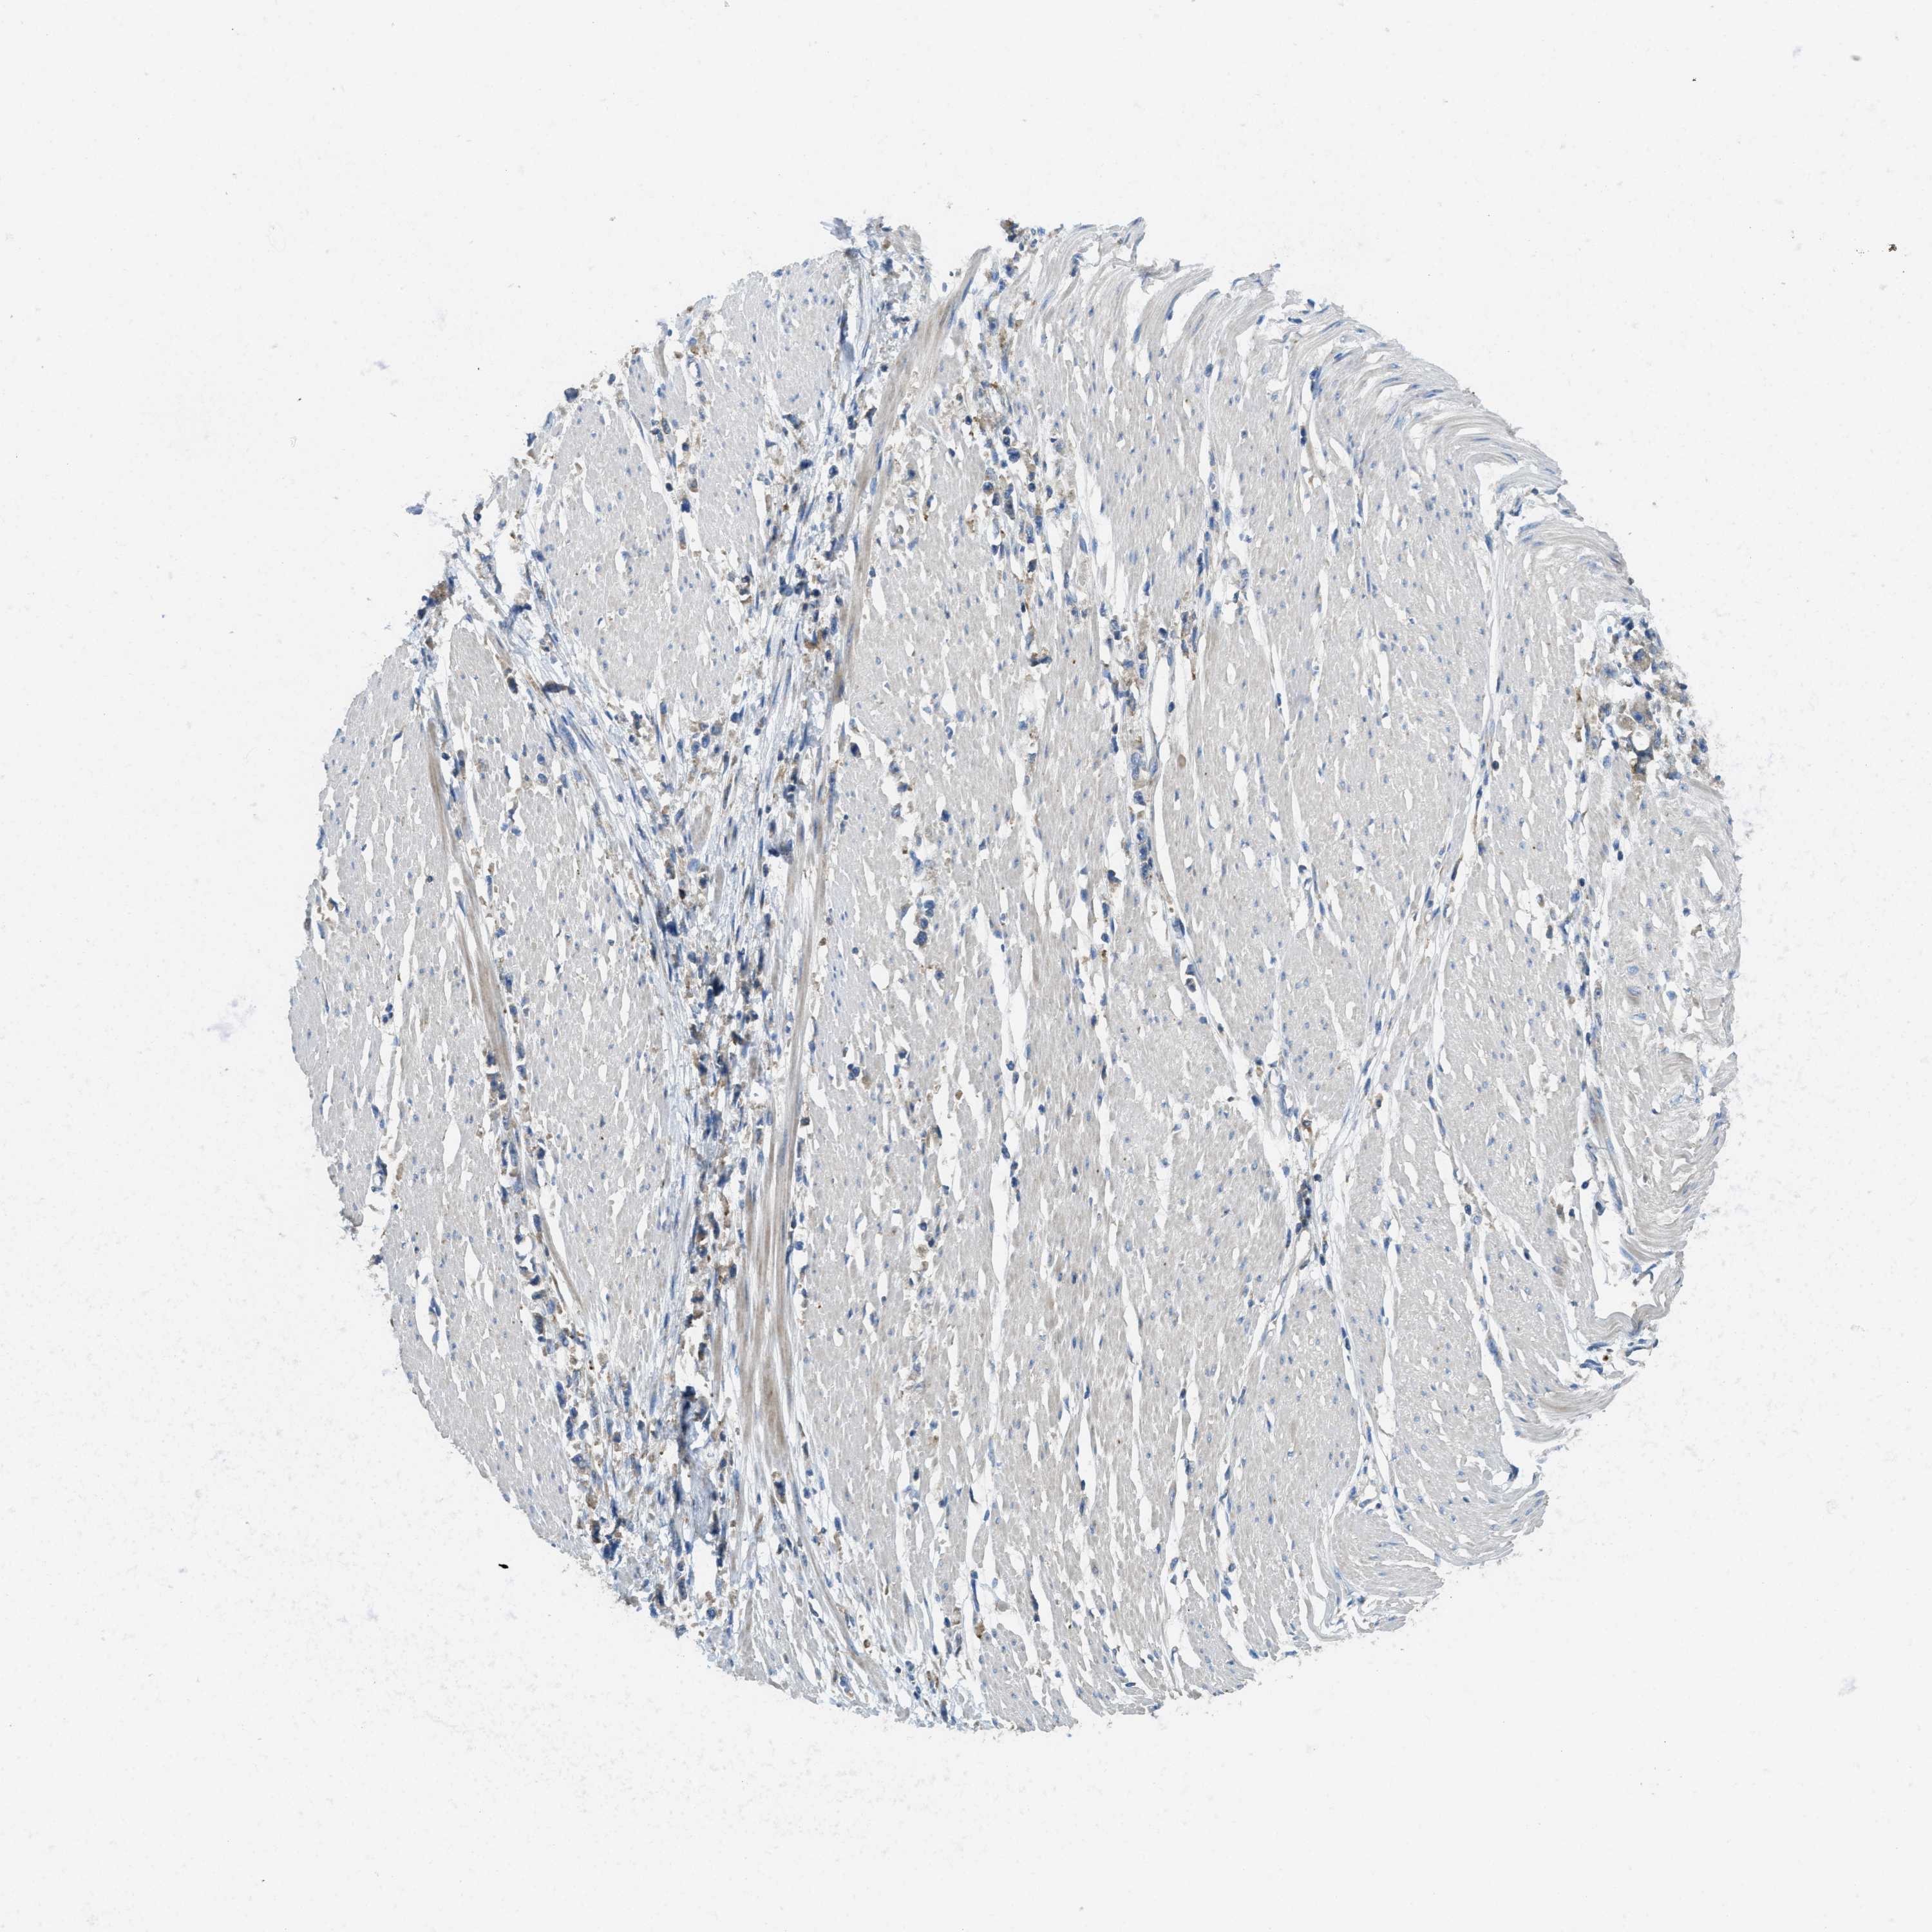

STOMACH CANCER - Protein expressioni

A mouse-over function shows sample information and annotation data. Click on an image to view it in a full screen mode. Samples can be filtered based on level of antibody staining by selecting one or several of the following categories: high, medium, low and not detected. The assay and annotation is described here.

Note that samples used for immunohistochemistry by the Human Protein Atlas do not correspond to samples in the TCGA dataset.

Antibody stainingi

Antibody staining in the annotated cell types in the current human tissue is reported as not detected, low, medium, or high, based on conventional immunohistochemistry profiling in selected tissues. This score is based on the combination of the staining intensity and fraction of stained cells.

Each image is clickable and will lead to virtual microscopy that enables deeper exploration of all samples and also displays staining intensity scores, fraction scores and subcellular localization as well as patient and tissue information for each sample.

Antibody HPA011276

Antibody HPA017062

Staining

High

Medium

Low

Not detected

Intensity

Strong

Moderate

Weak

Negative

Quantity

>75%

75%-25%

<25%

None

Location

Nuclear

Cytoplasmic/membranous

Cytoplasmic/membranous,nuclear

Adenocarcinoma, NOS

Adenocarcinoma, High grade